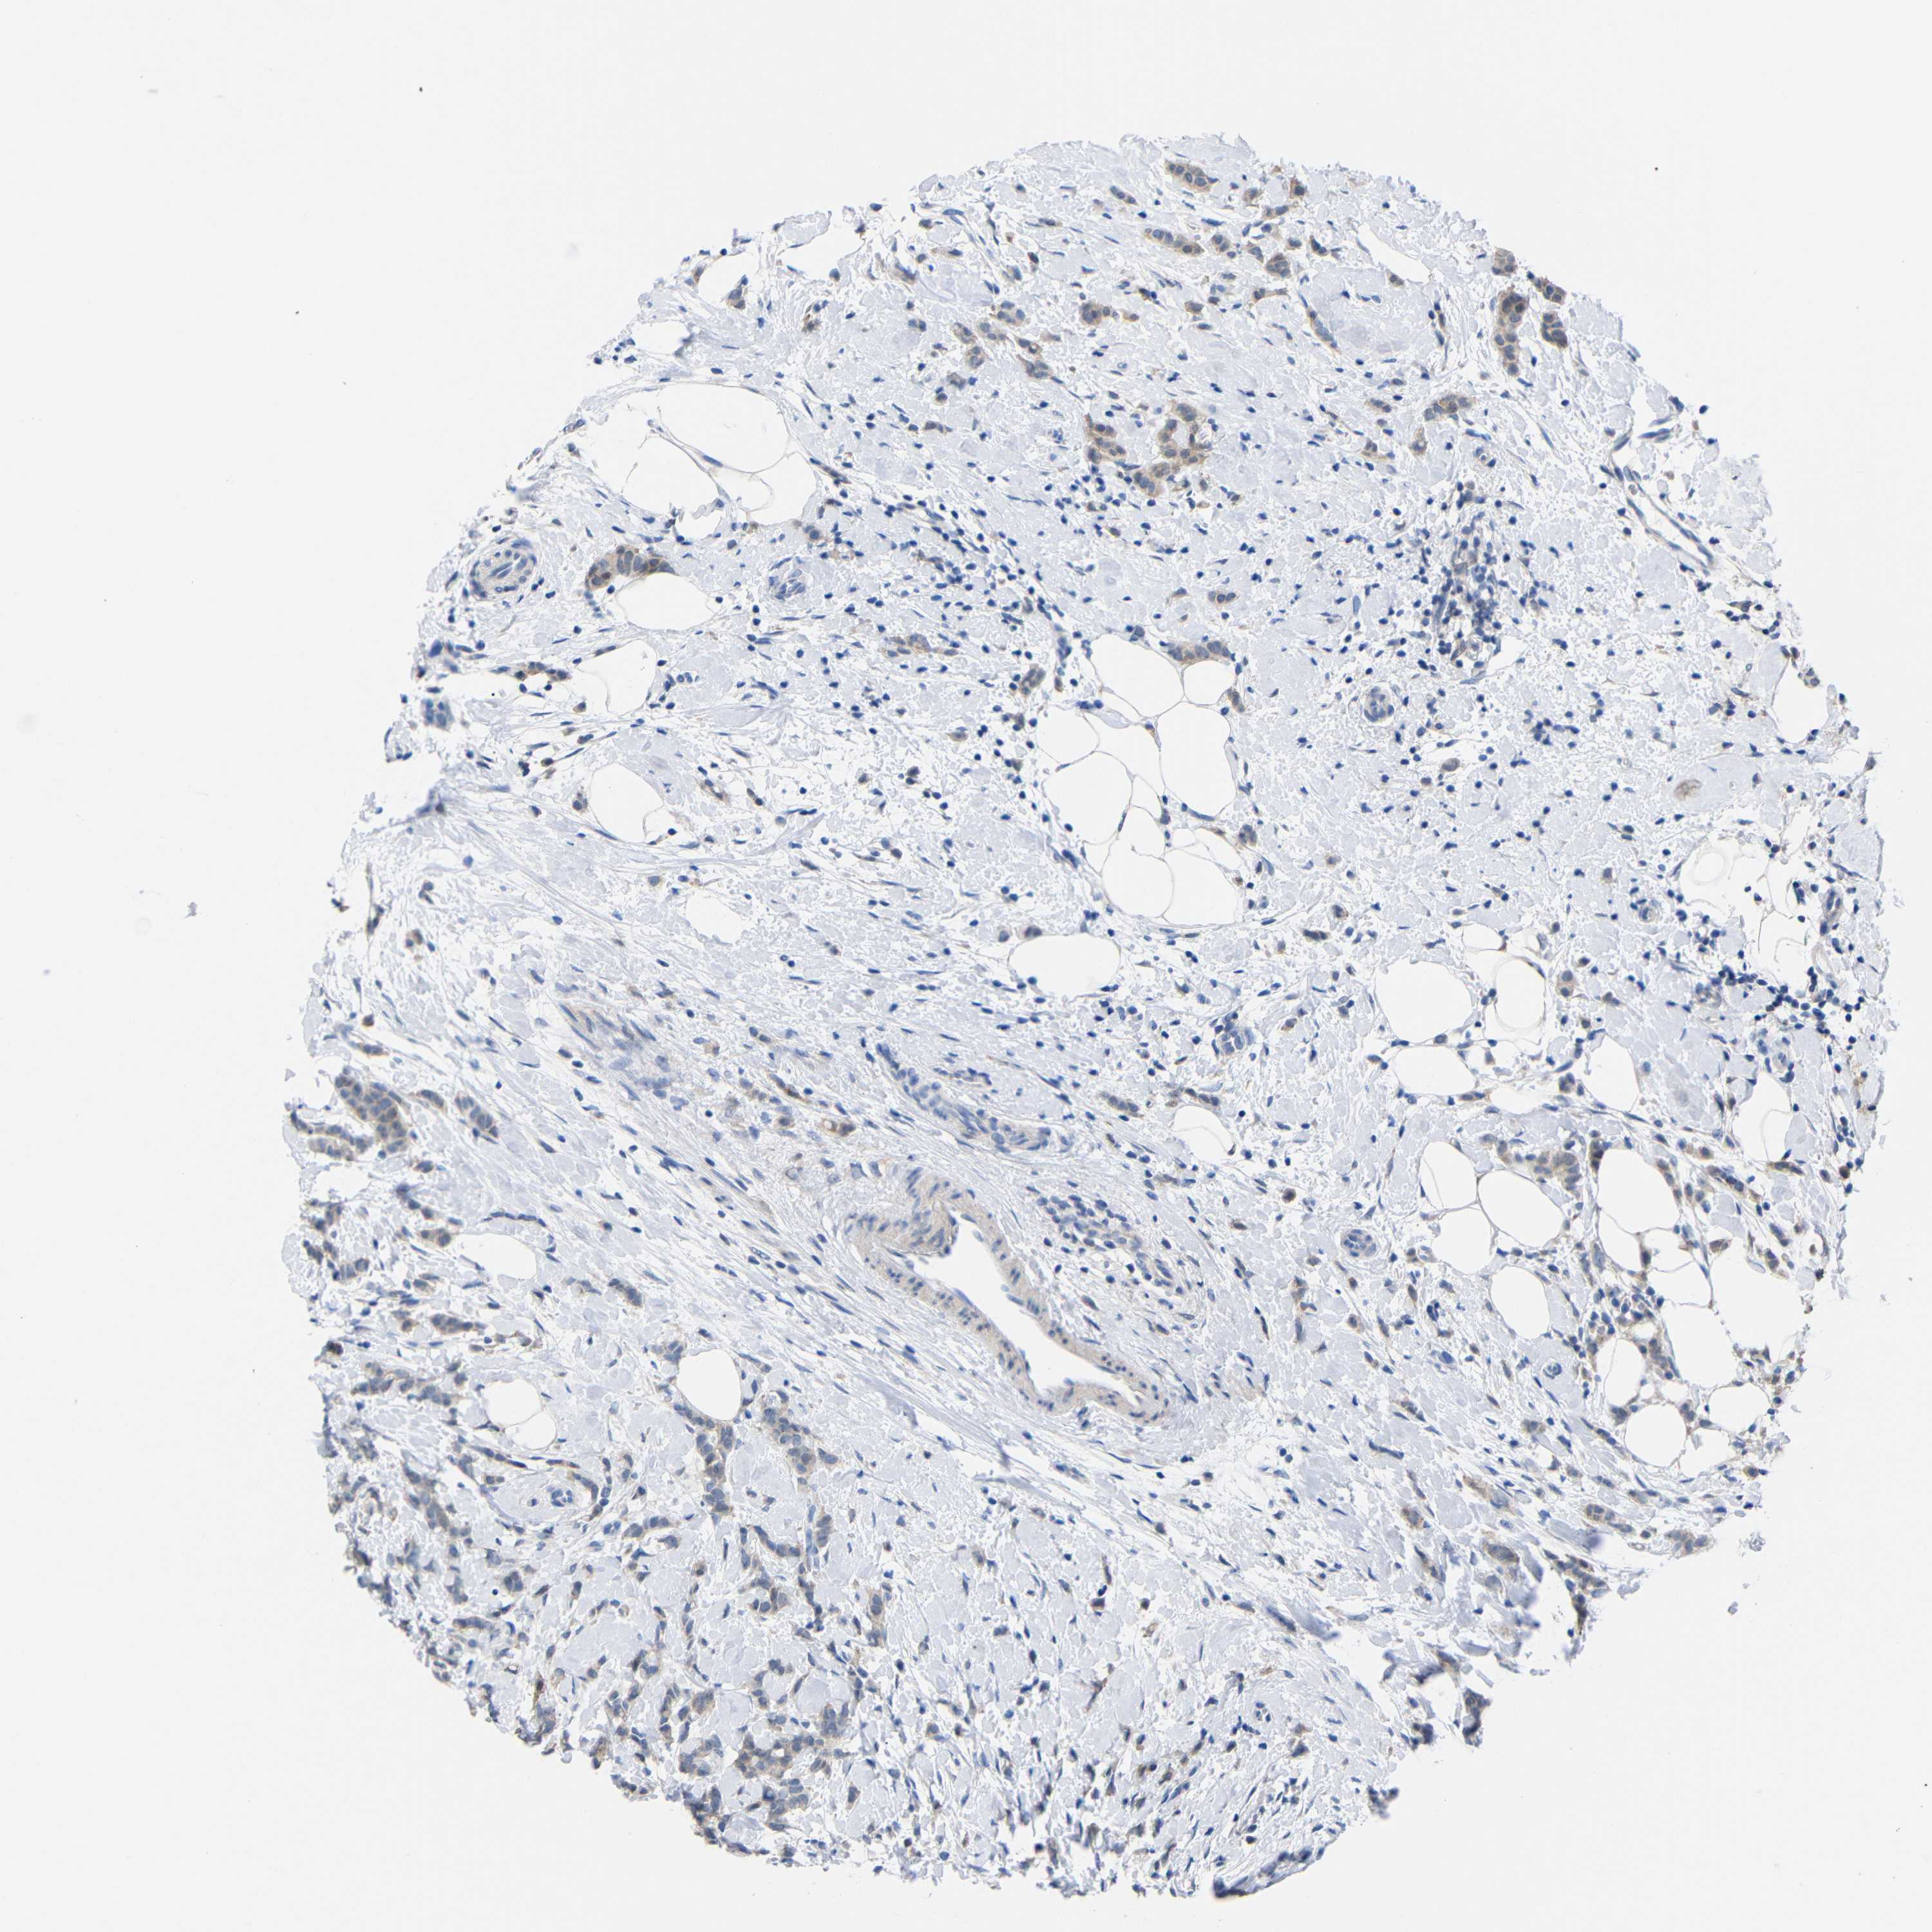

CANCER BREAST CANCER Show tissue menu

BRCA TCGA BRCA VALIDATION PROTEIN EXPRESSION

ANTIBODIES

AND

VALIDATION